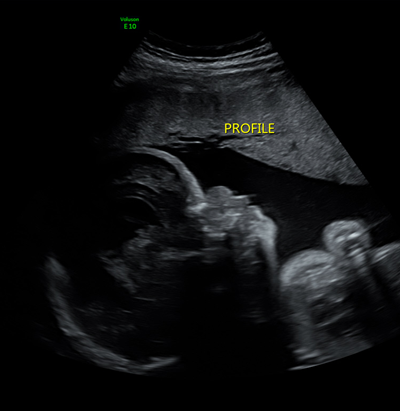

Caudal Regression Syndrome